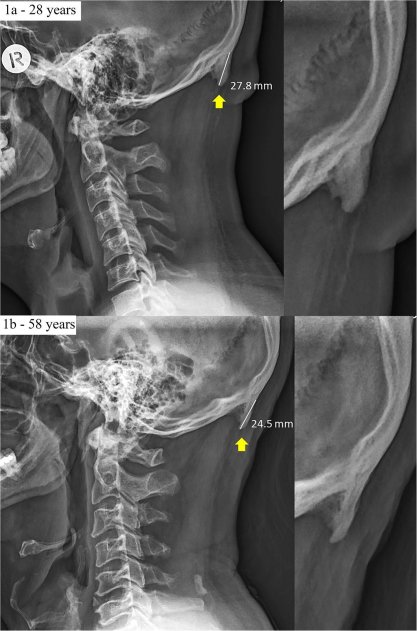

Исследование проведенное австралийскими учеными из University of the Sunshine Coast, Дэвидом Шахаром в 2016 году, показало, что из 218 обследованных пациентов 41% имеют костный нарост на черепе, связанный с длительным использованием смартфона. Другое исследование, проведённое в 2018 году, где обследовалось уже 1200 пациентов подтвердило эти выводы.

Исследование показало, что нарост чаще встречается у мужчин, чем у женщин, 67% против 20%. Самый длинный нарост в 35,7 мм был у мужчины и 25,5 мм у женщины. Больше всего подвержены этому изменению люди в возрасте от 18 до 30 лет (те кто чаще использует смартфон).

Это явление, получило название "текстовая шея", - это когда шея сильно напрягается, чтобы стабилизировать голову, в то время как голова направлена вниз для просмотра устройств, таких как смартфоны и планшеты. Такое положение головы становится дополнительной нагрузкой для мышц, соединяющих шею с затылком. В ответ на постоянное напряжение мышц, сухожилий и других соединительных тканей на черепе начинают формироваться новые выросты, которые расширяют площадь крепления мышц, обеспечивая им большую плотность и силу.